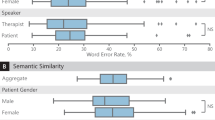

A team of resident doctors in internal medicine, physiatry, anatomical pathology and family medicine, and senior Canadian medical students created this dataset. The medical interviews were recorded in the format of Objective Structured Clinical Examinations (OSCE) 1 . 272 cases were simulated between the physician and the patient. These cases were recorded and classified into the categories of respiratory, musculoskeletal, cardiac, dermatological, and gastrointestinal diseases. However, the majority of simulations were respiratory cases. Please see Fig. 1 for a visual representation of the types of cases included. These audio recordings were then transcribed, manually corrected for speech to text errors, and an identifier was added to specify the speaker.

272 cases were simulated and recorded (please refer to Fig. 1 ). The focus of the dataset was respiratory cases (214 cases). In addition, 46 musculoskeletal cases, 5 cardiac cases, 6 gastrointestinal cases and 1 dermatology case were also simulated. Of the total simulated recordings, 57% of the cases involved a male physician and 43% involved a female physician. From the patient perspective, 55% of the simulated cases involved a male patient and 45% involved a female patient. The average duration of each conversation was 11 minutes and 56 seconds. For further details, please refer to Fig. 2 for a histogram of the number of cases corresponding to various lengths of time. The focus was on respiratory cases because most pandemics, including the COVID19 pandemic, are caused by droplet or airborne based respiratory diseases. Therefore, it is crucial to differentiate between a benign cause of malaise such as the common cold from a highly infectious and fatal cause such as COVID19 or Tuberculosis.